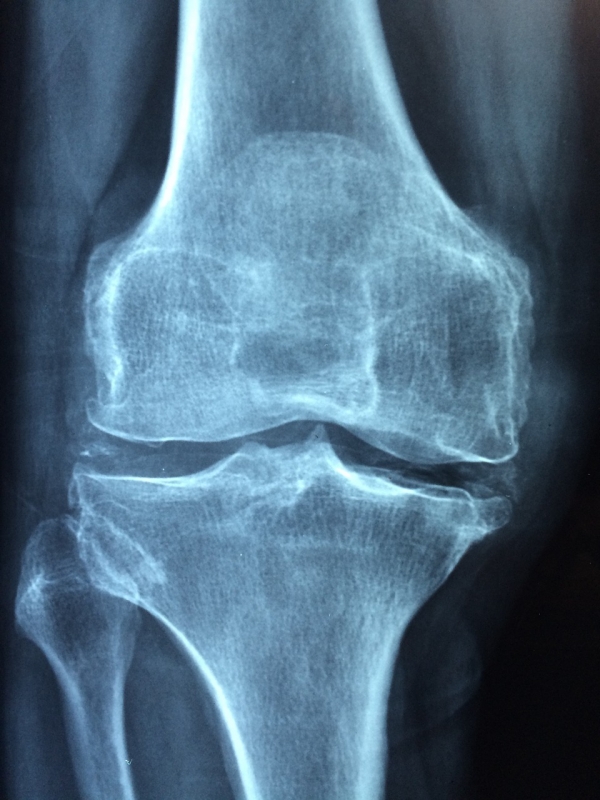

Специалисты утверждают, что регулярная физическая нагрузка минимизирует возможность развития артрита суставов. И речь идет не о тяжелых тренировках со штангой, а о элементарной зарядке и ходьбе.